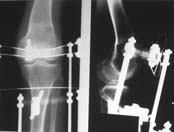

Пациент В. 53 лет, травма в феврале 2009. ДЗ. Открытый оскольчатый перелом нижней трети голени. При боли поступлении выполено ПХО, аппарат Илизарова. В последующем проводили ВХО, резекция костных отломков, укорочение 6 см, рана зажила. Была выполнена остеотомия большеберцовой кости в проксимальном отделе, резекция. Производилось тракция. На последних рентгенограммах выявлено, что одновременно с "выращиванием" регенерата произошло низведение надколенника на длину выращенного регенерата. Клинически: активное разгибание сохранено, объем движений в колене 180-110 градусов. Черными стрелками обозначен верхний край надколенника с одной и с другой стороны. Красная стрелка обозначает пальпируемую связку надколенника. Причина - остеотомия выше места прикрепления связки надколенника. Вопрос: была ли у кого подобная ситуация? Что делать? При первом обдумывании приходит решение: отсечение места прикрепления связки надколенника с костным блоком, перемещение на "правильное" место, укорочение сухожилия четырехглавой мышцы.

К сожалению, подобное осложнение "нет-нет да и возникает" при удлинении, коррекции деформации голени. В англоязычной литературе оно описано как "patella baja". Один из вариантов лечения - проксимальное перемещение надколенника приемами чрескостного остеосинтеза.

Я бы уменьшил диастаз между фрагментами сантиметра на два. Судя по снимкам, регенерат это может позволить.